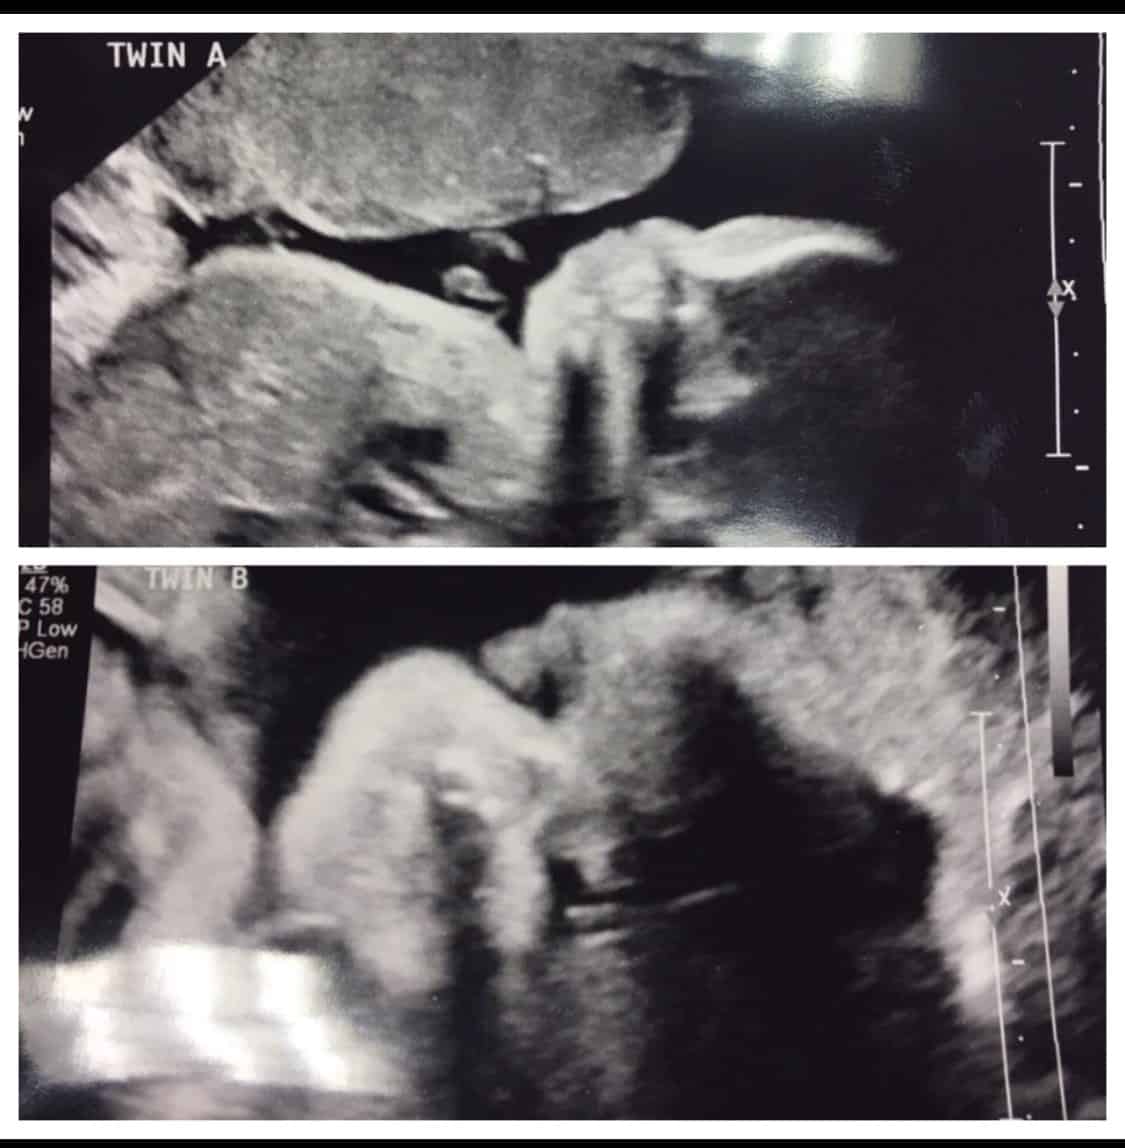

Ultrasound Photos at 30 Weeks Pregnant With Twins